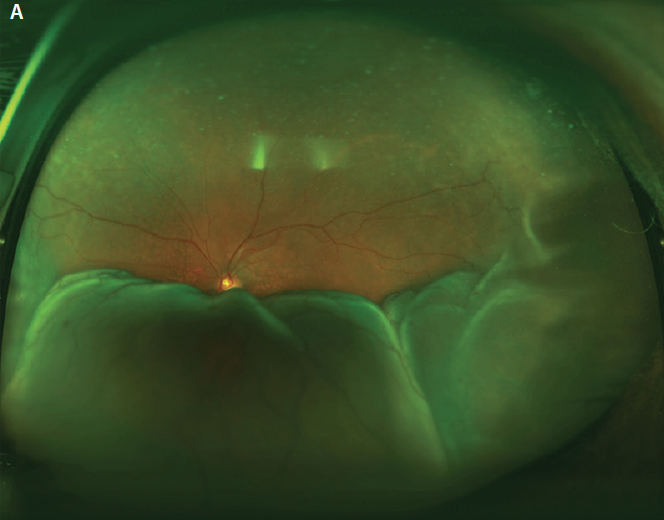

The disease course is typically relapsing and remitting. Gradual superior visual field loss is the most common initial complaint, but patients may also report blurred vision or metamorphopsia.2 The magnitude of choroidal elevation in UES is highly variable, but it typically begins in the periphery. Simultaneous exudative retinal detachment that can involve the macula may occur (Figure 1A). Deep retinal or subretinal exudates may appear prior to serous detachment, and optic nerve edema may be present.2,3 There may be mild to moderate vitreous cell.2 Hyperpigmented changes in the retinal pigment epithelium (RPE), termed leopard spots, and permanently reduced VA can occur with chronic disease (Figure 1B).4 Spontaneous resolution occurs in most cases but may take months or several years.2

Figure 1. Widefield color fundus photograph of an eye with UES depicting peripheral choroidal effusions with overlying serous retinal detachment (A). Postoperative appearance of the same eye after the creation of scleral windows shows flattening of the choroidal effusions and resolution of the serous retinal detachment with VA of 20/30. Persistent leopard spot hyperpigmentation is seen (B).